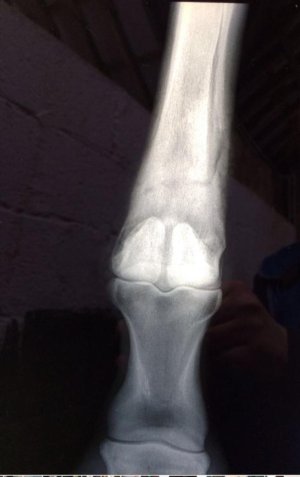

Omg I just realised whatever I just marked goes all the way up the leg 🙈

It does. So this horse started off with a splint bone fracture. At their 4 week xray check up we saw the horizontal crack all the way across the bone too. If that had moved or displaced the horse would be dead. Luckily for the horse we spotted it when we did, wrapped it back up for a few weeks, rehabbed and they raced on for another couple of years. It's a really weird rare one as they rarely crack horizontally without it being fatal. It wasn't seen at he first xray as you don't always see the full extent of the damage for a few days. So it will have been sitting their waiting to show.